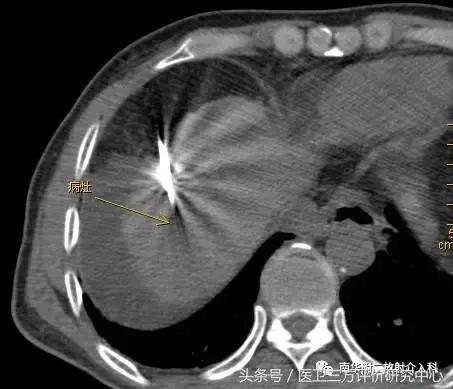

CT引导精准定位